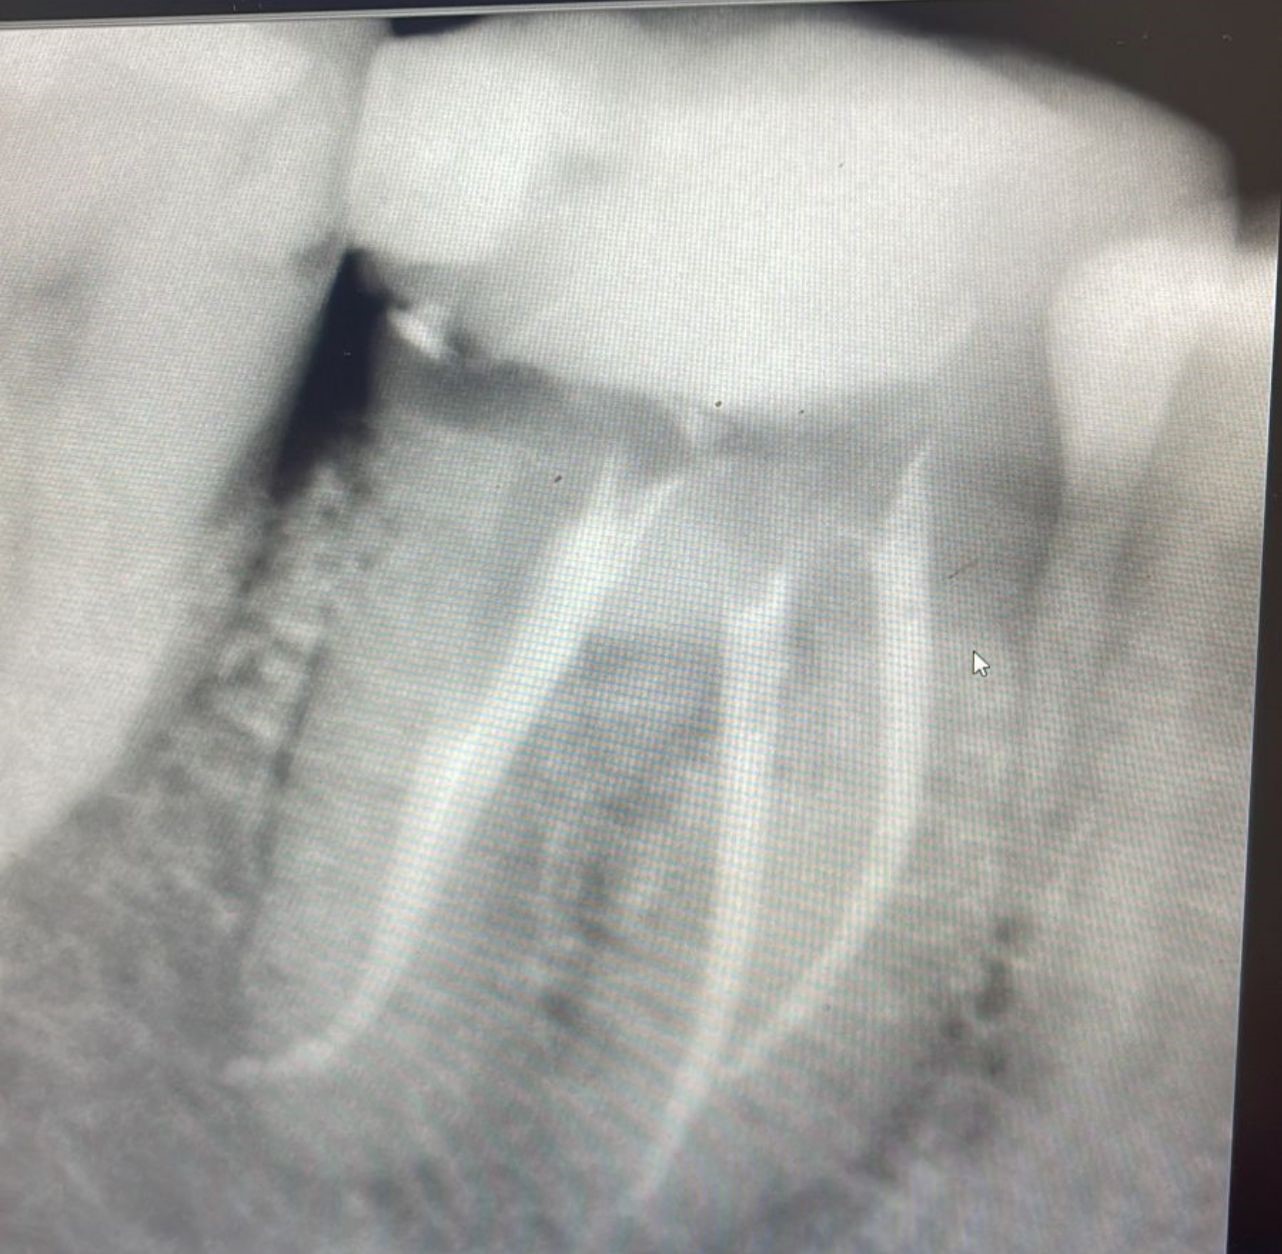

Galeria de Imagenes

Avances en procedicmiento de Endodoncia